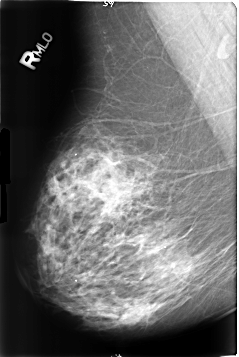

B_3174_1.RIGHT_MLO

RIGHT_MLO LINES 4632 PIXELS_PER_LINE 3096 BITS_PER_PIXEL 12 RESOLUTION 50 NON_OVERLAY